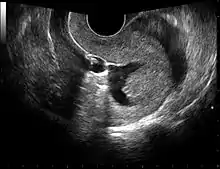

The examination can be performed by transabdominal ultrasonography, generally with a full bladder which acts as an acoustic window to achieve better visualization of pelvis organs, or by transvaginal ultrasonography with a specifically designed vaginal transducer. Transvaginal imaging utilizes a higher frequency imaging, which gives better resolution of the ovaries, uterus and endometrium (the fallopian tubes are generally not seen unless distended), but is limited to depth of image penetration, whereas larger lesions reaching into the abdomen are better seen transabdominally. Having a full bladder for the transabdominal portion of the exam is helpful because sound travels through fluid with less attenuation to better visualize the uterus and ovaries which lies posteriorly to the bladder. The procedure is by definition invasive when performed transvaginally. Scans are performed by health care professionals called sonographers, or gynecologists trained in ultrasound.